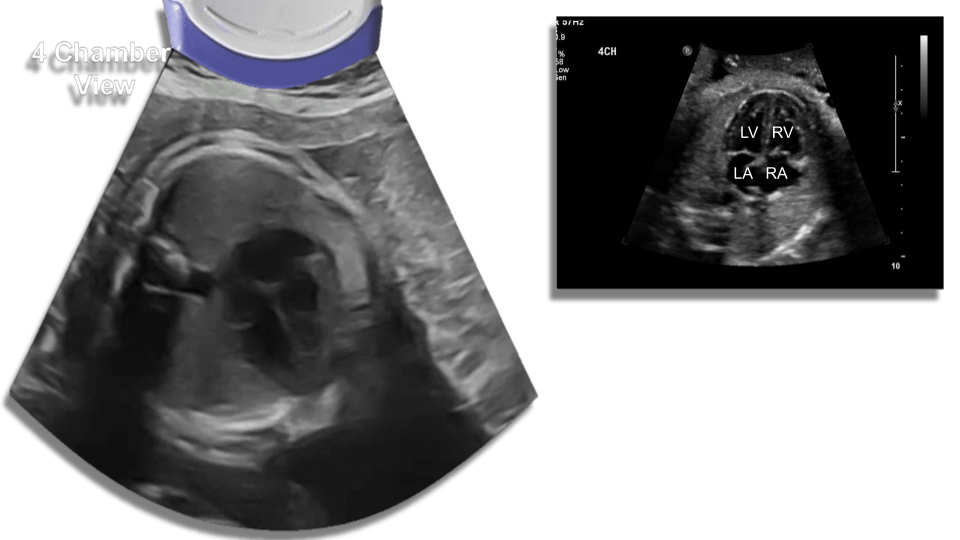

Heart size relation to chest (hear takes up 1/3 of the chest with the apex pointing to the left).

Four chamber view, also asses the lung parenchyma.

Aortic Arch

Perform cardiac m-mode for fetal heart rate look out for arrhythmias, tachycardia, bradycardia or lack of cardiac activity (fetal demise.)